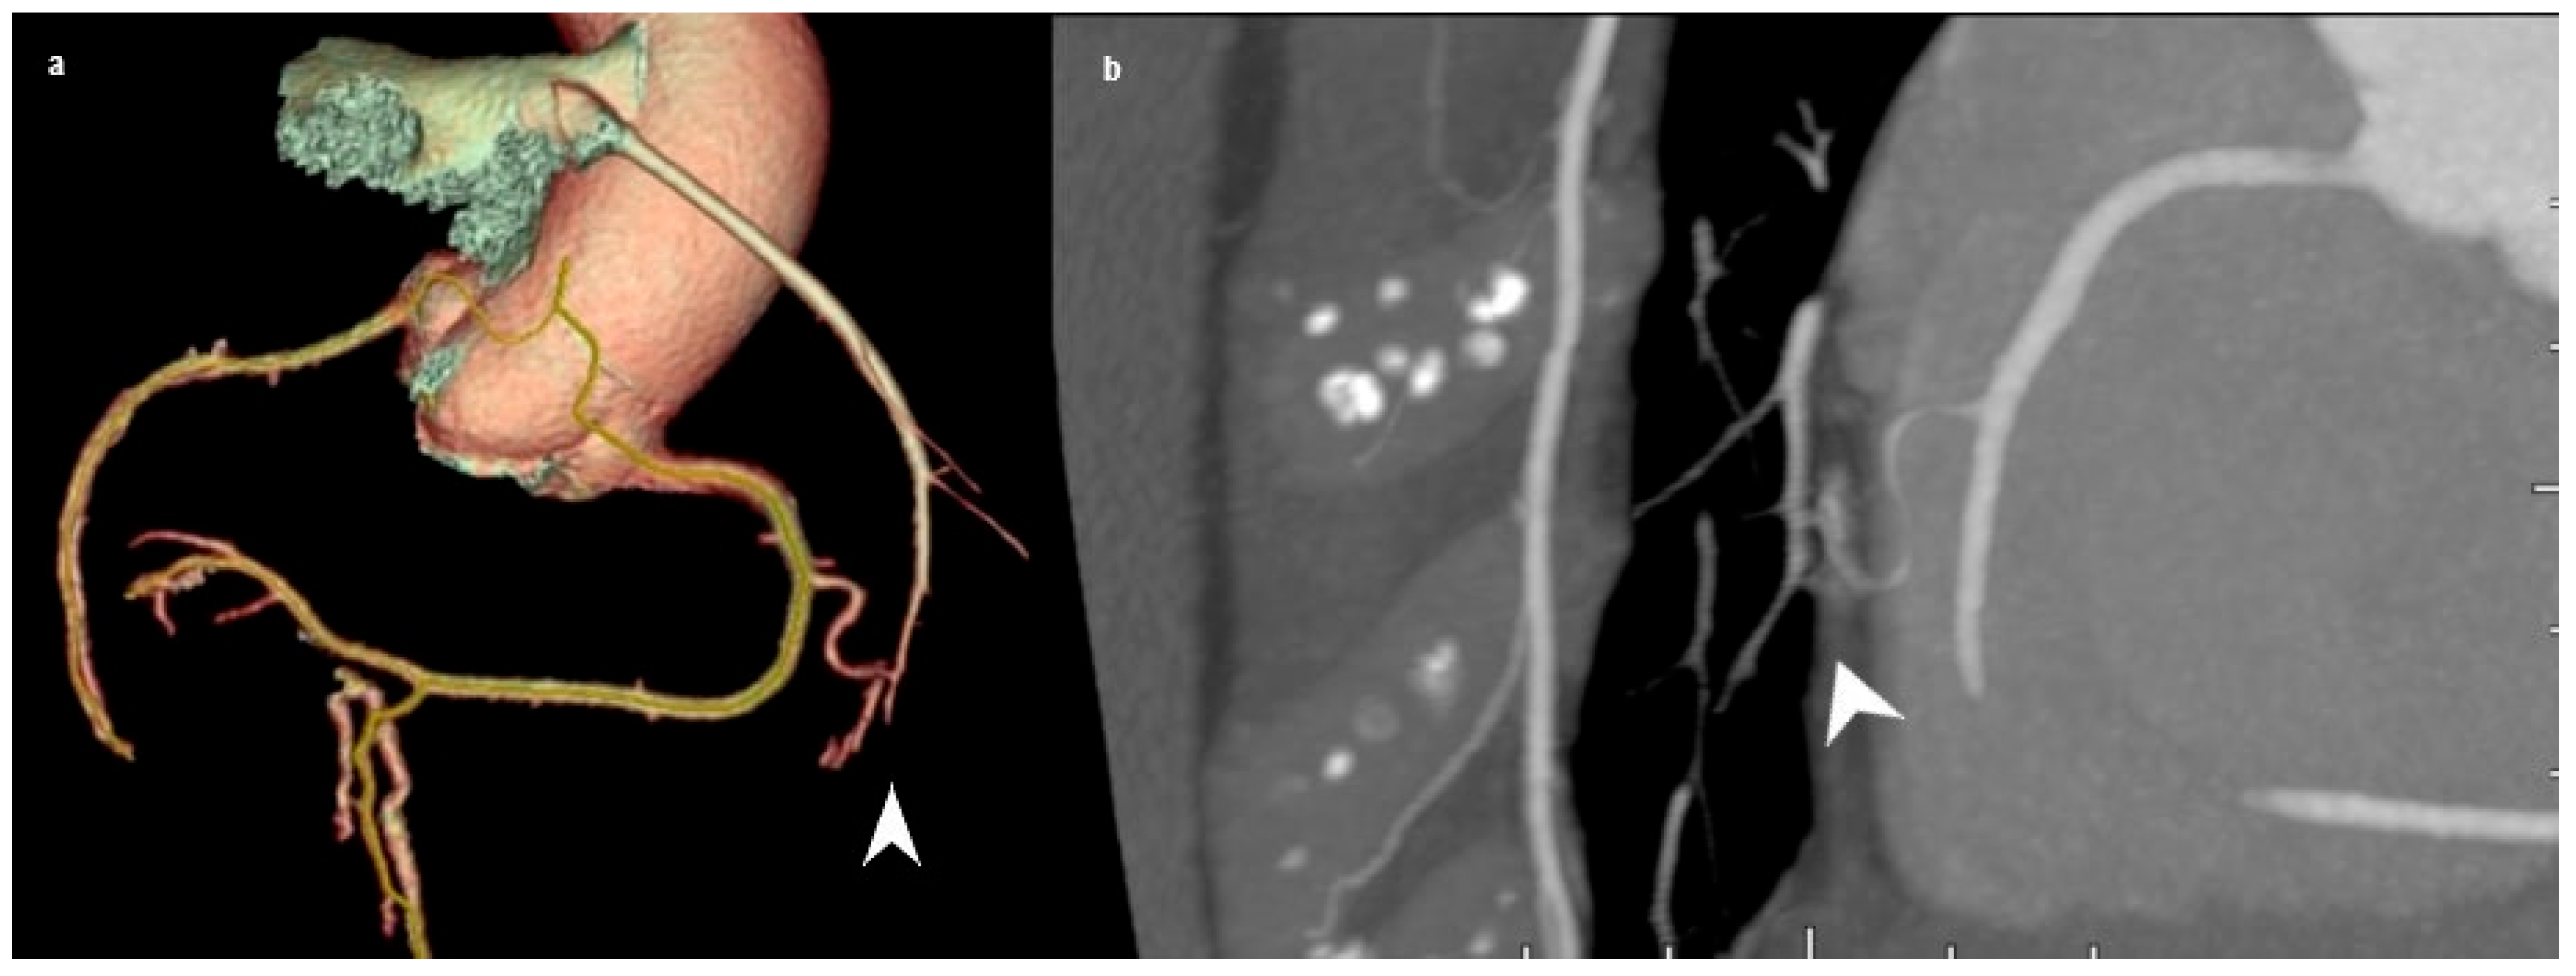

3.3. Coronary Arteriovenous Fistula